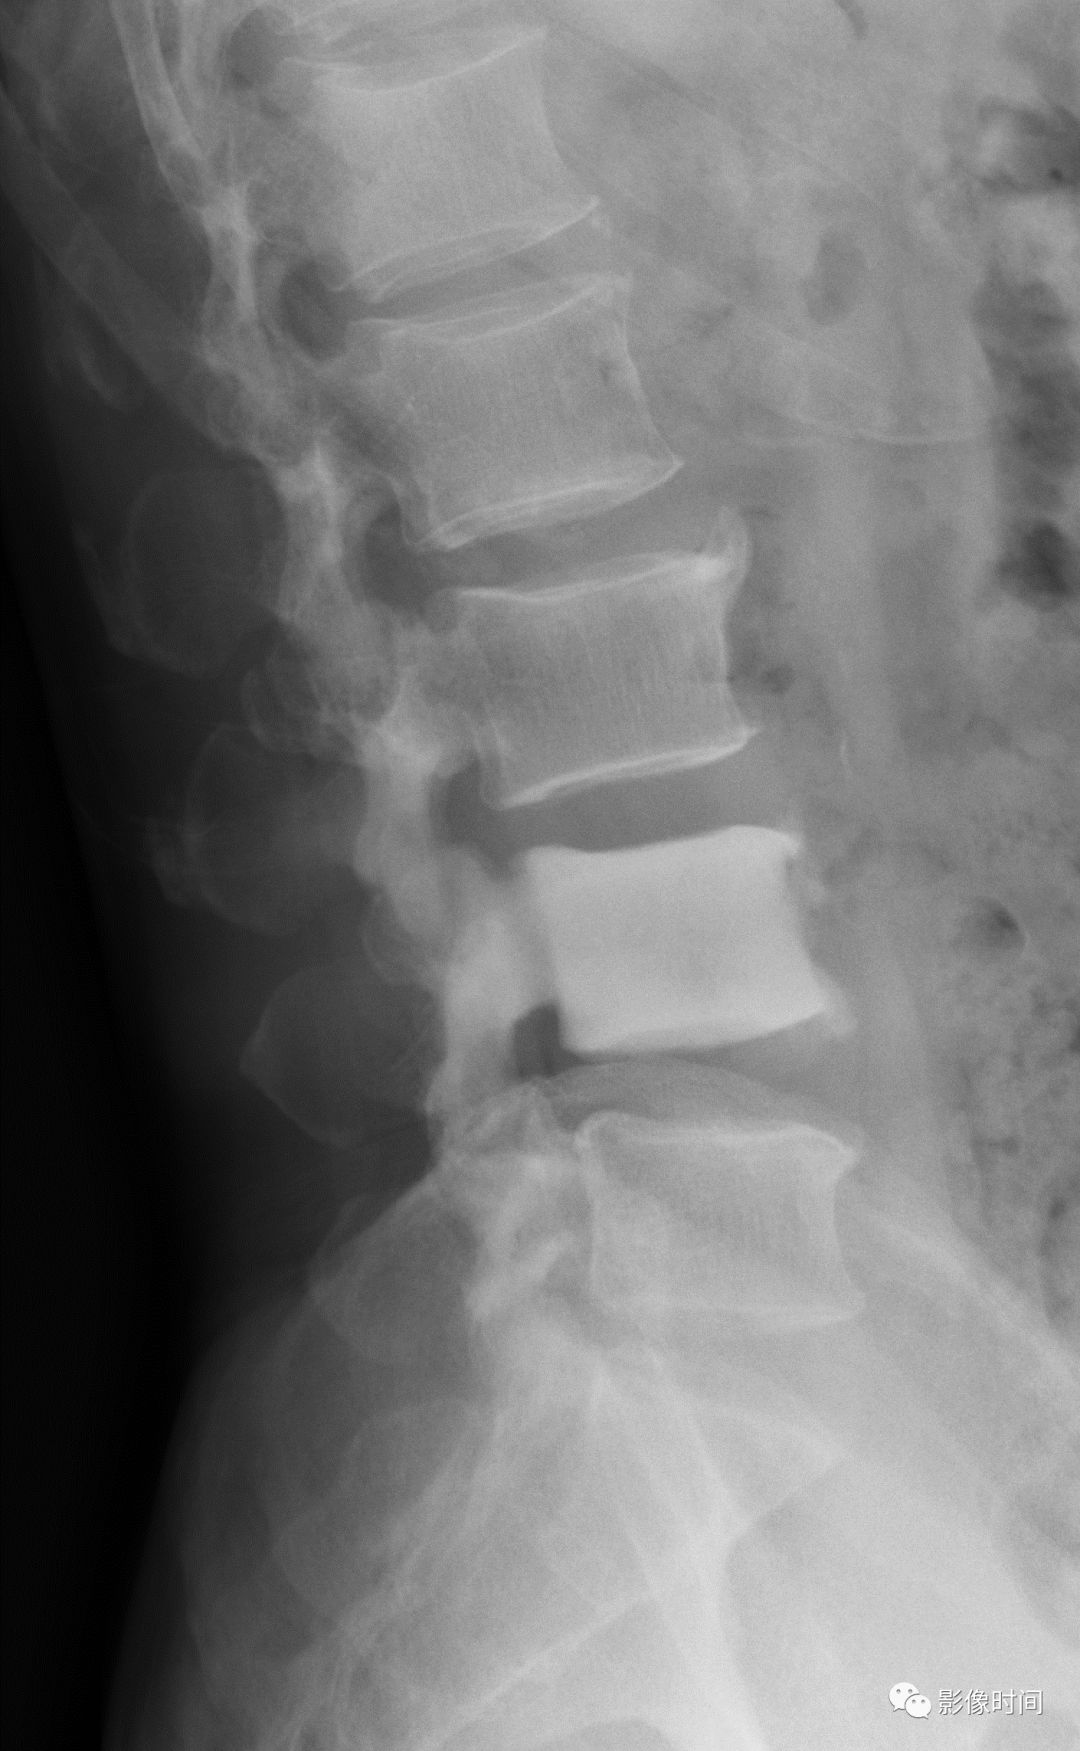

10栅栏征

栅栏征(The Palisade sign),也称灯芯绒椎体(corduroy vertebra)或灯芯绒征(corduroy sign)

脊椎椎体因病变导致骨小梁吸收、稀疏,为满足承重需要,存留的纵向骨小梁粗大;粗大骨小梁间以细条状密度减低区,形成栅栏样影像,故称栅栏征或灯芯绒椎体。

栅栏征最常见于血管瘤,以单个脊椎居多;骨质疏松如泛发性骨质增生症、老年性骨质疏松等亦可呈现此类表现,一般见于下胸椎、上部腰椎的多个椎体,只是伴有普遍的骨密度减低。有时自颈椎至腰椎全部椎体均出现栅栏征。栅栏征主要见于椎体。

典型病例

病例 1,脊柱血管瘤。胸腰椎 CT 冠状位、矢状位 MPR 重建示胸 12 椎体松质骨密度降低,其中可见粗大骨小梁呈栅栏状。

病例 2,67 岁女性,椎体血管瘤。腰椎侧位片示胸 12 及腰 3 椎体呈现栅栏征,磁共振检查证实为血管瘤。

病例 3,泛发性骨质增生症,男,47 岁。A-C.颈椎、胸椎、腰椎侧位片,显示所有椎体纵向骨小梁粗大、稀疏;粗大骨小梁间以细条状密度减低区,呈栅栏征。D-G.胸、腰椎 MR 冠状、矢状位图像,粗大、稀疏的示纵向骨小梁呈低信号,在邻近富脂肪骨髓信号衬托下呈典型的栅栏征